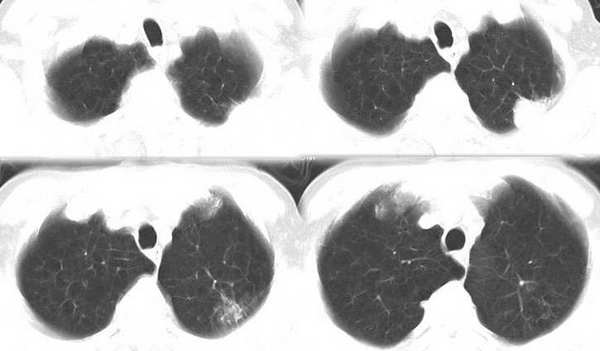

薄层扫描

左肺上叶尖后段胸膜下软组织密度结节,形态不规则,可见浅分叶,短毛刺,与胸膜广基相连,夹角成锐角。复查10个月后明显增大。考虑周围型肺癌。

左肺尖后段胸膜下软组织密度肿块,形态不规则,有分叶,局部胸膜增厚,病灶周围见点片状影,与二月份片比较,肿块增大,考虑周围型肺癌伴阻塞性炎症,穿刺活检要有困难,因后方是肩胛骨躲不开.